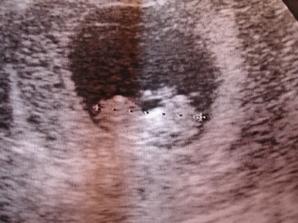

Naši malou kočičku jsme vytvořili po urputné snaze v září 2007 (skoro na den přesně 10 let od začátku love story s tatínkem 🙂 Termín porodu vypočítán na 5.6.2008 Pozitivní těhotenský test 27.9. 2007. Potvrzené těhotenství z krve 1.10.2007 - 365 hCg. 4.10.2007 - 985 hCg. Hospitalizace ve nemocnici - čeká se na uložení těhotenství - v děloze, hurá!! Další hospitalizace 11.11.2007 - bolest břicha. Po týdnu propuštěna, vše v pořádku. Další hospitalizace - tvrdnutí břicha 19.2.2008 - propuštěna po MĚSÍCI. No a naposledy na dva dny do nemocnice v dubnu, kvůli tlaku a točení hlavy.